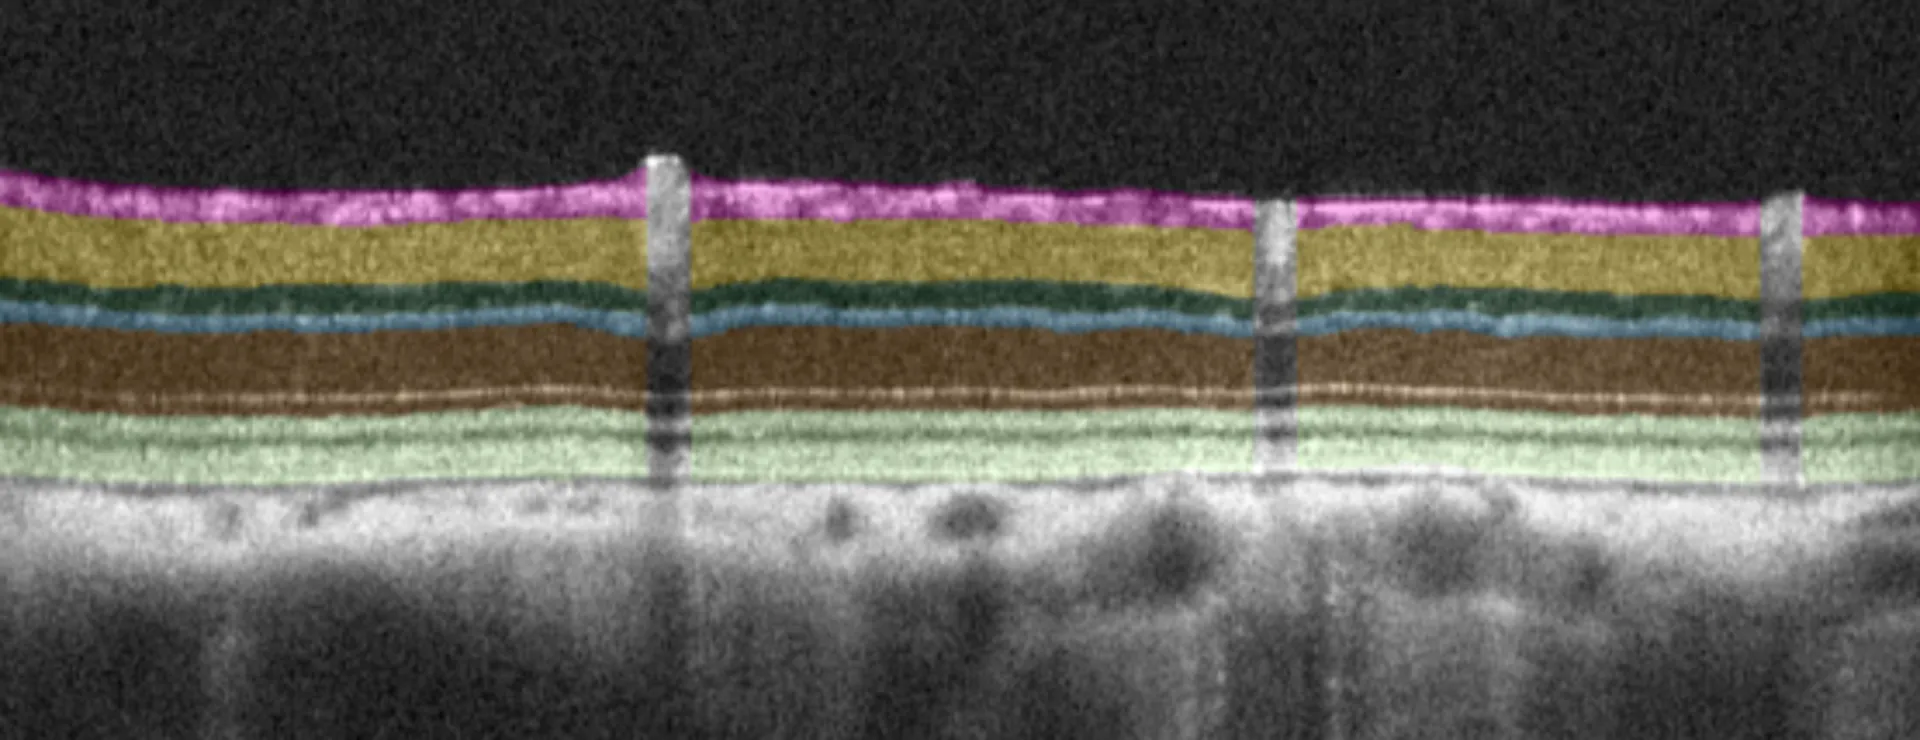

Experimentica employs state-of-the-art in vivo imaging for longitudinal monitoring of NAION pathology. SD-OCT enables cross-sectional visualization of the optic nerve head and retina to assess edema and retinal layer thinning (Ragauskas et al., 2018). Retinal ganglion cell (RGC) function is evaluated using pattern electroretinography (pERG), visual acuity and contrast sensitivity (OMR). RGC loss is confirmed by immunolabeling in retinal flatmounts, and optic nerve damage is assessed through histological sectioning and staining.

– Quantitative data from in vivo imaging and AI-driven segmentation analysis (SD-OCT)

Quantitative readouts enabled by proprietary AI-driven algorithms.